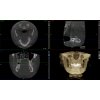

3D SNÍMKY VE VYSOKÉ KVALITĚ

Vysoce kvalitní snímky CT skeneru Planmed Verity® vizualizují i ty nejmenší kostní struktury s minimálním rušením. Izotropní rozlišení 200 μm, pokročilé algoritmy zpracování obrazu a pevné ucycení pacienta umožňují snímkování ve vysoké kvalitě. S algoritmem Planmeca CALM ™ lze zabránit zbytečným opakovaným expozicím citlivé oblasti hlavy a krku. Kromě toho je zobrazování ultra nízkou dávkou cenným doplňkem ke studiu oblasti hlavy, kde je třeba věnovat zvláštní pozornost minimalizaci radiační dávky pacienta.

Díky umístění typu walk-in je zobrazování oblasti hlavy rychlé a efektivní. Pohodlí pacienta je maximalizováno dvěma pohodlnými možnostmi polohování vsedě, polohovacími podnosy, polohovací kamerou a lasery. Zobrazovací protokoly jsou pro ně optimalizovány tak, aby pokrývaly typické oblasti zájmu, jako jsou dutiny, maxilofaciální oblast a zuby.